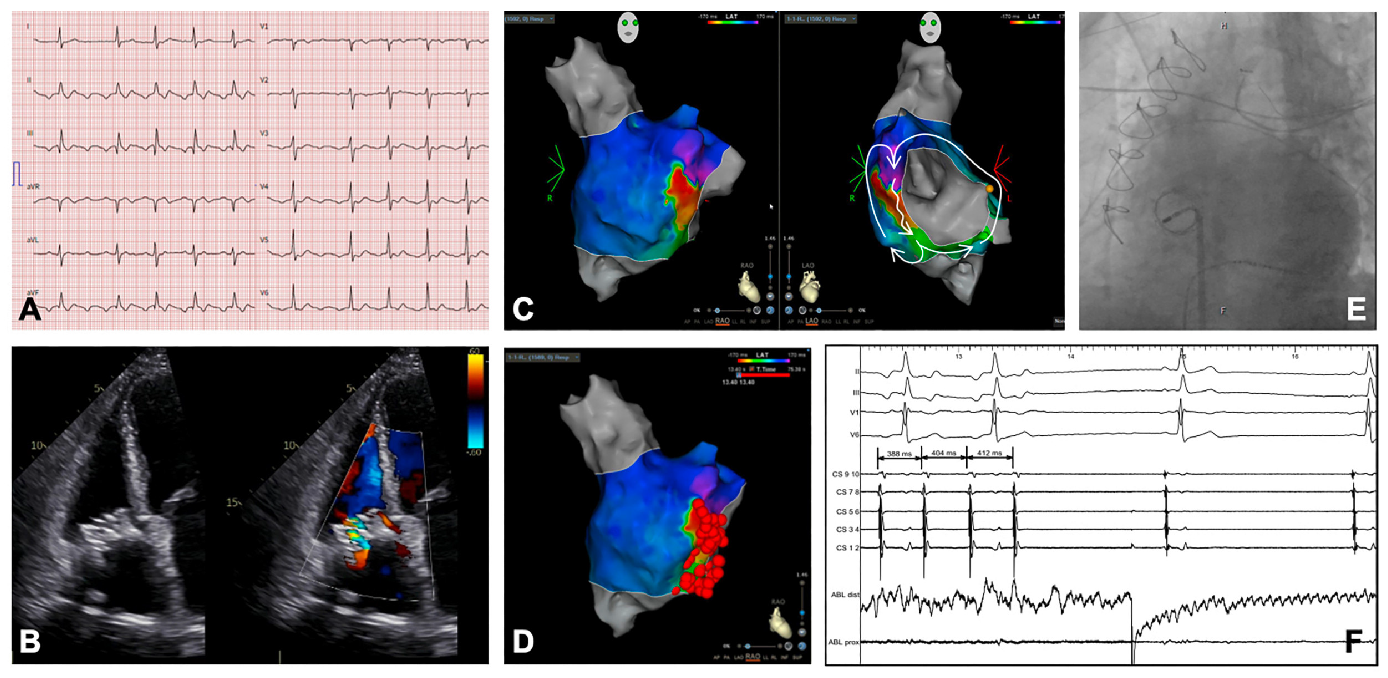

Right-Sided Atrial Flutter Ablation After Tricuspid Valve-in-Valve Replacement

Case Report